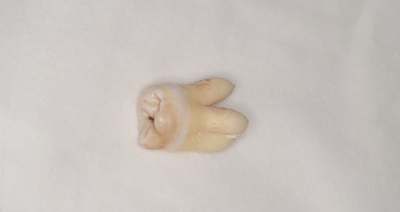

CASE 1

| 年齢・性別 | 30代・女性 |

| 主訴 | 左右に分けて親知らずを抜きたい、できれば痛くなく抜きたい |

| 親知らずのはえ方 | 完全に出ていてまっすぐはえている |

| 抜歯期間 | 15分 |

| 抜歯費用 | 約2,000円(保険内) |

| 抜歯内容 |

何度か虫歯になり痛みはないが早めに抜きたい。 完全に頭が出ているため歯ぐきを切ったり骨を削らずに抜歯しました。 根の形も単純なため抜歯自体は5分もかからず上下ともに終わりました。 術後痛みや腫れも出ていません。 抜歯後は感染をしやすいため必ず抗生物質を飲み切ってください。 |